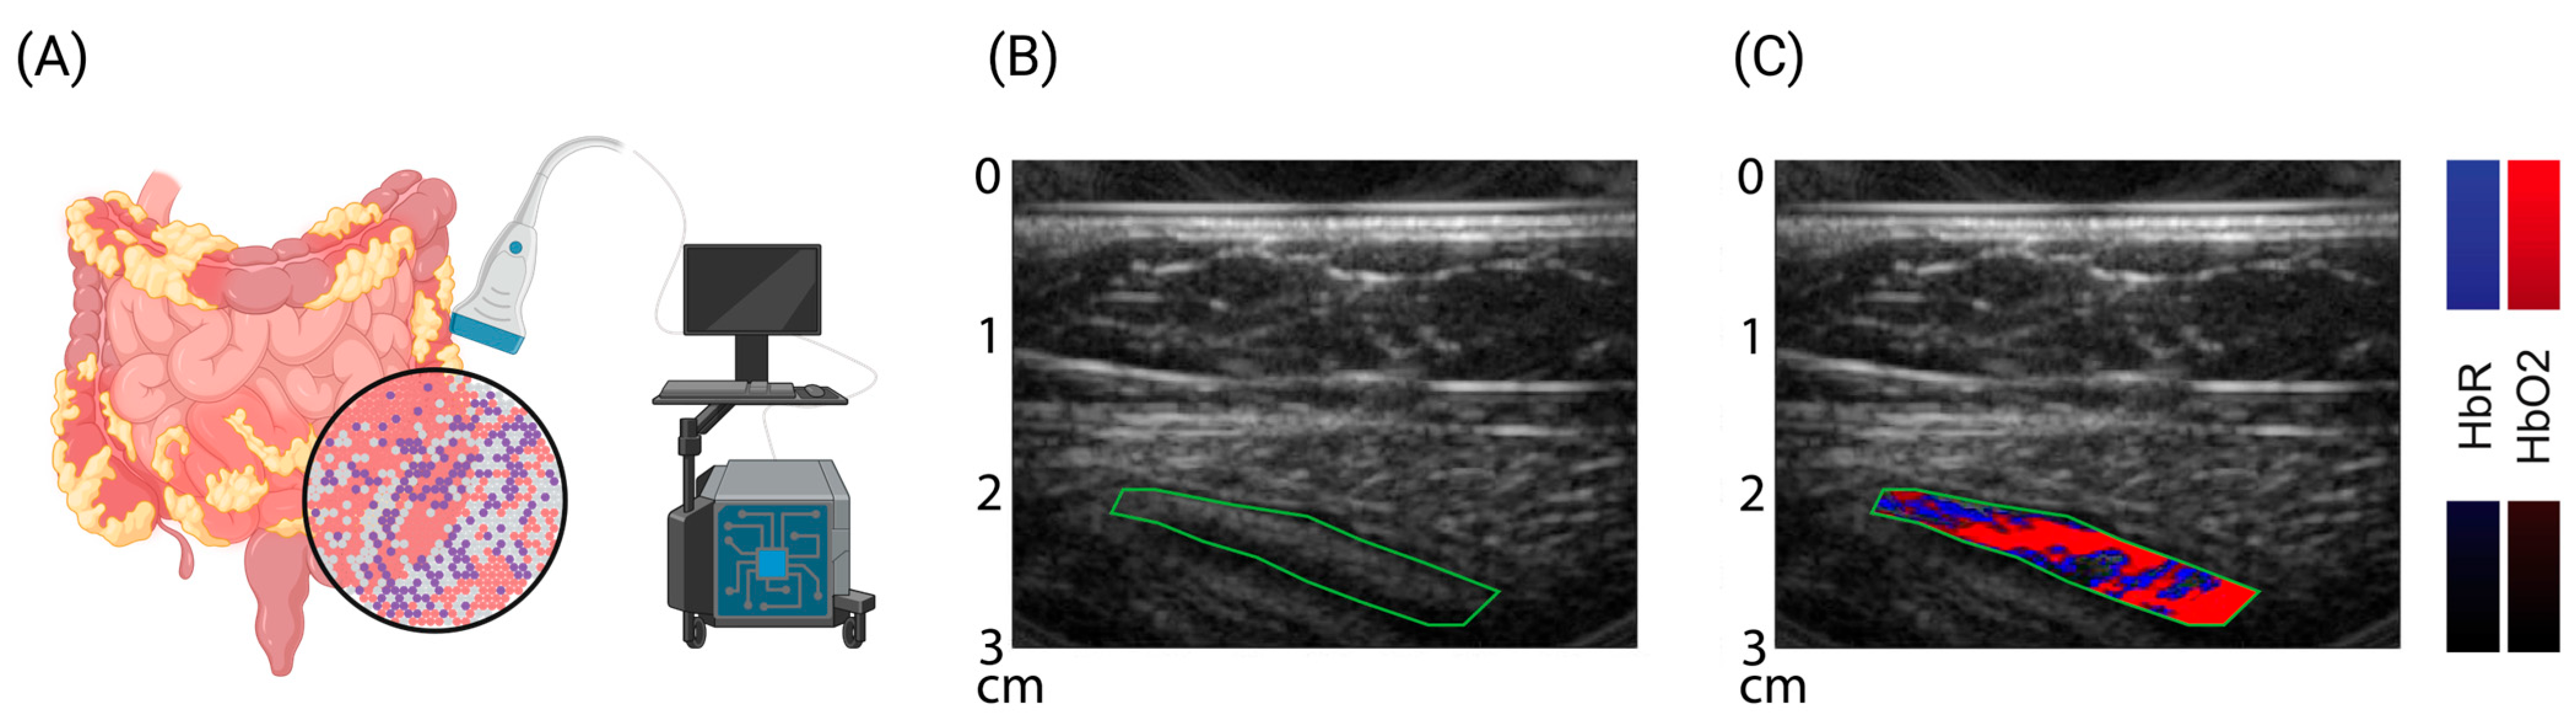

In murine models of colitis, disease severity can be measured by means of increased signal intensities for hemoglobin transabdominally in vivo [118,119], and by using transrectal guidance, changes in the intestinal wall thickness and vessel architecture can even be detected [120]. Furthermore, OAI technologies have the potential to identify intestinal inflammation and fibrosis to characterize intestinal strictures in mice [121,122]. The first pilot studies in adult patients with Crohn’s disease used a handheld OAI system to carry out so-called multispectral optoacoustic tomography (MSOT) to assess disease activity in comparison to clinical, laboratory, endoscopic, and conventional ultrasound [123,124]. The MSOT signal levels for hemoglobin correlated well with disease phenotype with minimal effort from the patient, and with high accuracy in the detection of remission and active disease [124]. In addition, studies on the precision of MSOT for imaging the human intestine showed resilient data [125], and the option of imaging luminal contrast agents throughout the intestinal tract opens the door to further translational applications and functional assessment of the gastrointestinal tract [126,127,128]. Such approaches might help to delineate complications likes fistulae, which are common manifestations in CD patients [129,130]. Early pilot studies in other pediatric conditions (neuromuscular disorders) were promising [131,132,133], and the first study in pediatric patients with UC and CD confirmed previous findings in adults [134] (Figure 2).

Figure 2.

Multispectral optoacoustic imaging—molecular sensitive ultrasound. (A) Cartoon of bedside multispectral optoacoustic tomography (MSOT) to assess molecular tissue composition. (B,C) Exemplary reflected-ultrasound computed tomography (RUCT) and MSOT images of a pediatric patient with ulcerative colitis. RUCT enables real-time guidance of the investigator. Spectral unmixing of MSOT data allows differentiation and quantification of oxygenated (red) and deoxygenated (blue) blood within the bowel wall (green, region of interest). Increased levels of hemoglobin correlate with disease activity and might serve as surrogate biomarkers. Created with https://www.biorender.com/ (accessed on 22 January 2024).

Currently, the multicenter approval study of MSOT in adult patients with Crohn’s disease is closed (https://euphoria2020.eu/, accessed on 22 January 2024), and further longitudinal studies in pediatric IBD are expected. For the manifestation of Crohn’s disease in the upper gastrointestinal tract, the integration of OAI in (capsule) endoscopic devices might allow the molecular assessment of the disease similarly to prior studies of the esophagus [135,136,137].